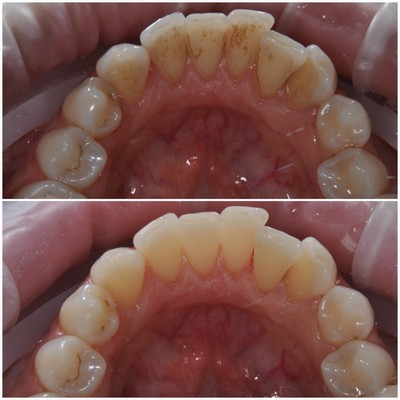

Врачи-стоматологи единодушны в том, что самым эффективным способом лечения периодонтита является комплексный подход, включающий как медикаментозную терапию, так и хирургические методы. На начальных стадиях заболевания важно провести профессиональную чистку зубов, чтобы удалить зубной налет и камень, что способствует уменьшению воспаления. Врач может назначить антибиотики для борьбы с инфекцией и противовоспалительные препараты для снятия симптомов. В более запущенных случаях может потребоваться хирургическое вмешательство, такое как кюретаж или резекция корня зуба, что позволяет устранить очаги инфекции и восстановить здоровье тканей. Регулярные профилактические осмотры и поддерживающая терапия также играют ключевую роль в предотвращении рецидивов и поддержании здоровья десен.

Регулярно посещайте стоматолога для профессиональной чистки зубов. Это поможет удалить зубной налет и камень, которые могут способствовать развитию периодонтита.

Обратите внимание на свою гигиену полости рта. Чистите зубы дважды в день и используйте зубную нить для удаления остатков пищи и налета между зубами.